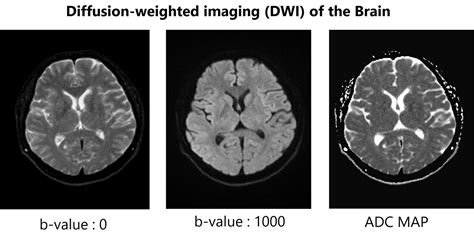

what is dti mri

what is dti mri. There are any references about what is dti mri in here. you can look below.